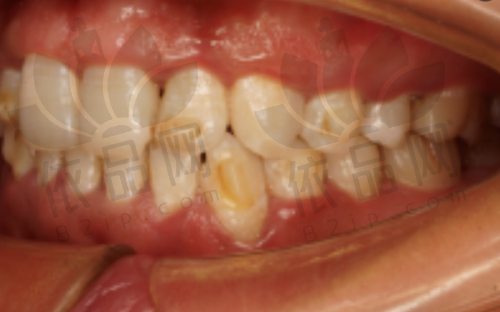

在牙齿矫正方面,哈尔滨优贝口腔医院拥有隐适美、正雅、适美乐等多种矫正方法。不同的矫正方法适用于不同年龄段、不同牙齿状况的患者。隐适美矫正器采用透明材质,美观舒适,几乎不会影响患者的日常生活和社交活动。正雅矫正器则具有个性化定制的特点,能够根据患者的牙齿情况进行精细设计,达到更好的矫正成效。适美乐矫正器价格相对较为亲民,对于一些经济条件有限但又有矫正需求的患者来说,是一个不错的选择。

这些矫正方法不仅矫治器美观舒适,而且矫正成效显著。许多患者在哈尔滨优贝口腔医院进行牙齿矫正后,牙齿变得整齐美观,面部轮廓也得到了改善。比如,一些青少年患者因为牙齿不齐而产生自卑心理,通过在该医院进行牙齿矫正,重新找回了自信,变得更加开朗活泼。